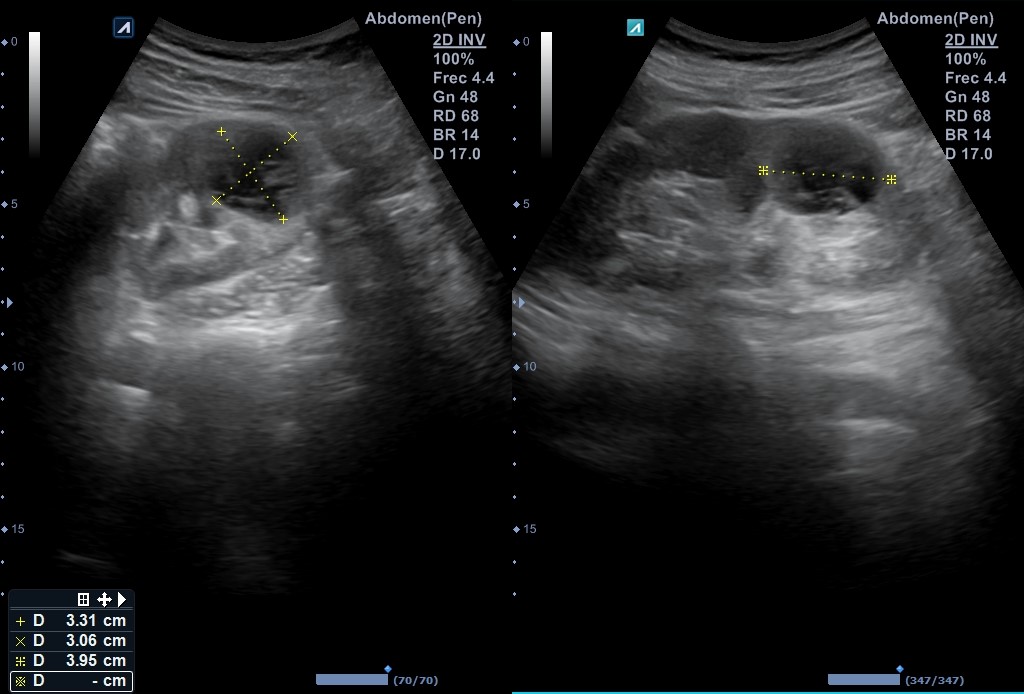

Se reevalúa a la paciente en consulta 2 semanas después, que refiere mejoría sintomática. Se repite la ecografía evidenciándose imágenes de riñón izquierdo sano y ausencia de la lesión previamente descrita.

Tras ser valorada por el Servicio de Urología, se solicita TC abdomino-pélvico con contraste, donde se confirma la ausencia de colección y en el que describieron como únicos hallazgos patológicos una nefrolitiasis izquierda de 5 mm sin uropatía obstructiva asociada y múltiples quistes renales bilaterales.

De este modo se confirma el diagnóstico de sospecha de absceso renal, con buena evolución y actualmente resuelto.